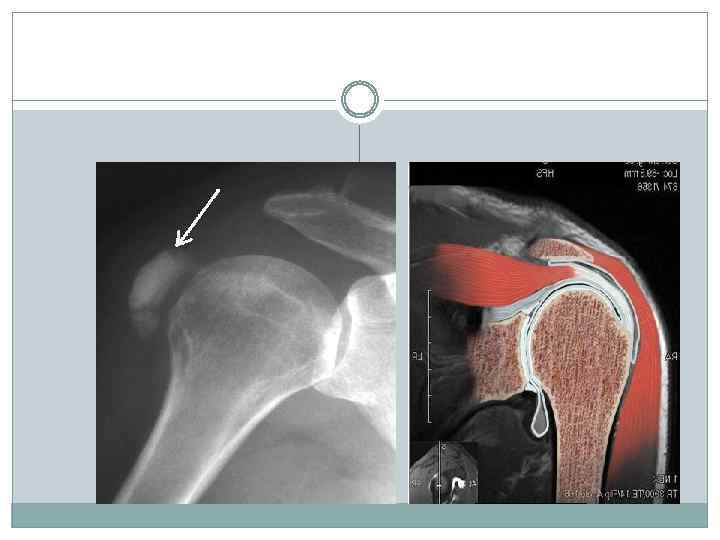

Периартроз плечевого сустава Синдром, характеризующийся болями и скованностью в плечевом суставе, связанный с различными по природе заболеваниями. Частота — 80% всех случаев болезненности плечевого сустава. Преобладающий возраст — старше 40 лет. Преобладающий пол — мужской. Плечелопаточный болевой синдром относится к мышечным синдромам в области руки

Периартроз плечевого сустава Патогенез При выполнении работы, при боковом отведении и ротации плеча, совершаемых часто и в большом объеме, возникают условия длительной травматизации связочно-сухожильного участка сустава и синовиальных сумок, что и вызывает их дегенерацию с реактивным асептическим воспалением. При формировании заболевания определяются выраженные дегенеративные изменения, преимущественно в сухожилиях надостной и подлопаточной мышц, одновременно может быть деформирующий артроз плечевого сустава. В некоторых случаях возрастной дегенеративный процесс приводит к образованию дефекта в связочносухожильном участке капсулы сустава, соединяющего полость сустава с подакромиальной сумкой. При поднимании максимально отведенной в сторону руки большой бугорок плечевой кости подходит под акромион и клювовидно акромиальную связку, что и создает условия для травматизации (сдавливания) капсулы плеча. Поэтому не случайно термин «периартроз плечевого сустава» – понятие собирательное для ряда заболеваний в области плечевого сустава (дельтовидный бурсит, субакромиальный бурсит).

Диагноз Периартроз плечевого сустава диагностируют на основании выявленных нарушений специфических функций движения рукой: невозможность боковых отведений, ротации плеча, симптома закладывания руки за спину. Рентгенологические признаки: склеротические изменения площадки большого бугорка плечевой кости и наличие теней известковых отложений различного размера, формы и плотности. Для формирования профессионального периартроза плечевого сустава характерно постепенное начало Отсутствие подъема температуры, увеличения СОЭ, сдвига в лейкоформуле.